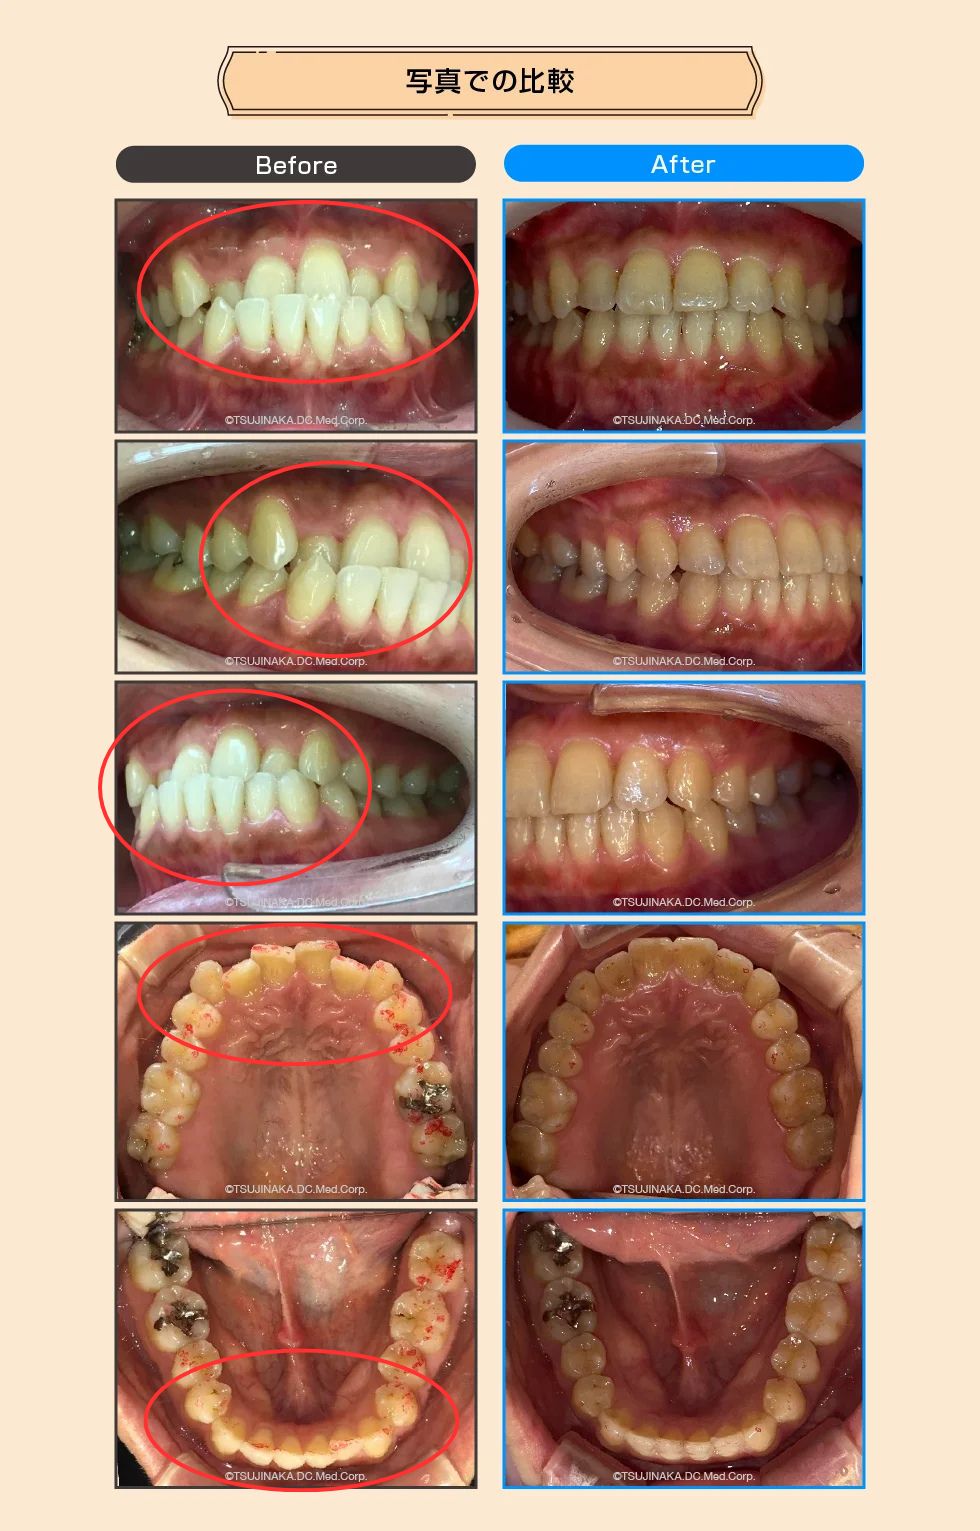

【症例No.5437】歯の不揃いを直したい

歯並びの不揃い(受け口・前歯のデコボコ)が気になるとのことでご相談いただきました。マウスピース型矯正装置を用いた矯正治療により、反対咬合の改善を目指し、必要に応じて顎間ゴムの併用やIPR(歯の隣接面をわずかに削合)を行いました。

| 診断名 | 反対咬合/叢生 |

| 治療内容 | マウスピース型矯正装置(インビザライン)を用いた矯正治療。反対咬合の改善を目指し、必要に応じて顎間ゴムを併用。歯列スペース確保のためIPRを実施しました。 |